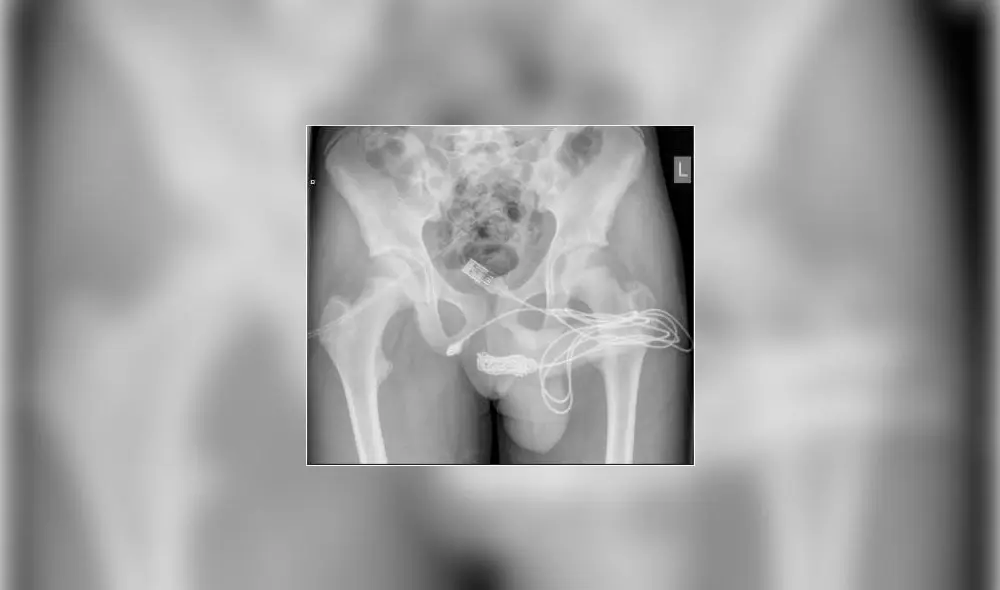

Los médicos tuvieron que operar al joven para retirar el cable USB | Foto: ScienceDirect

Tras escuchar su testimonio, los médicos le practicaron una radiografía pélvica simple. “Los intentos manuales y endoscópicos de extracción no tuvieron éxito, por lo que se realizó uretrostomía penoescrotal” para remover el cable, añade el papel científico.